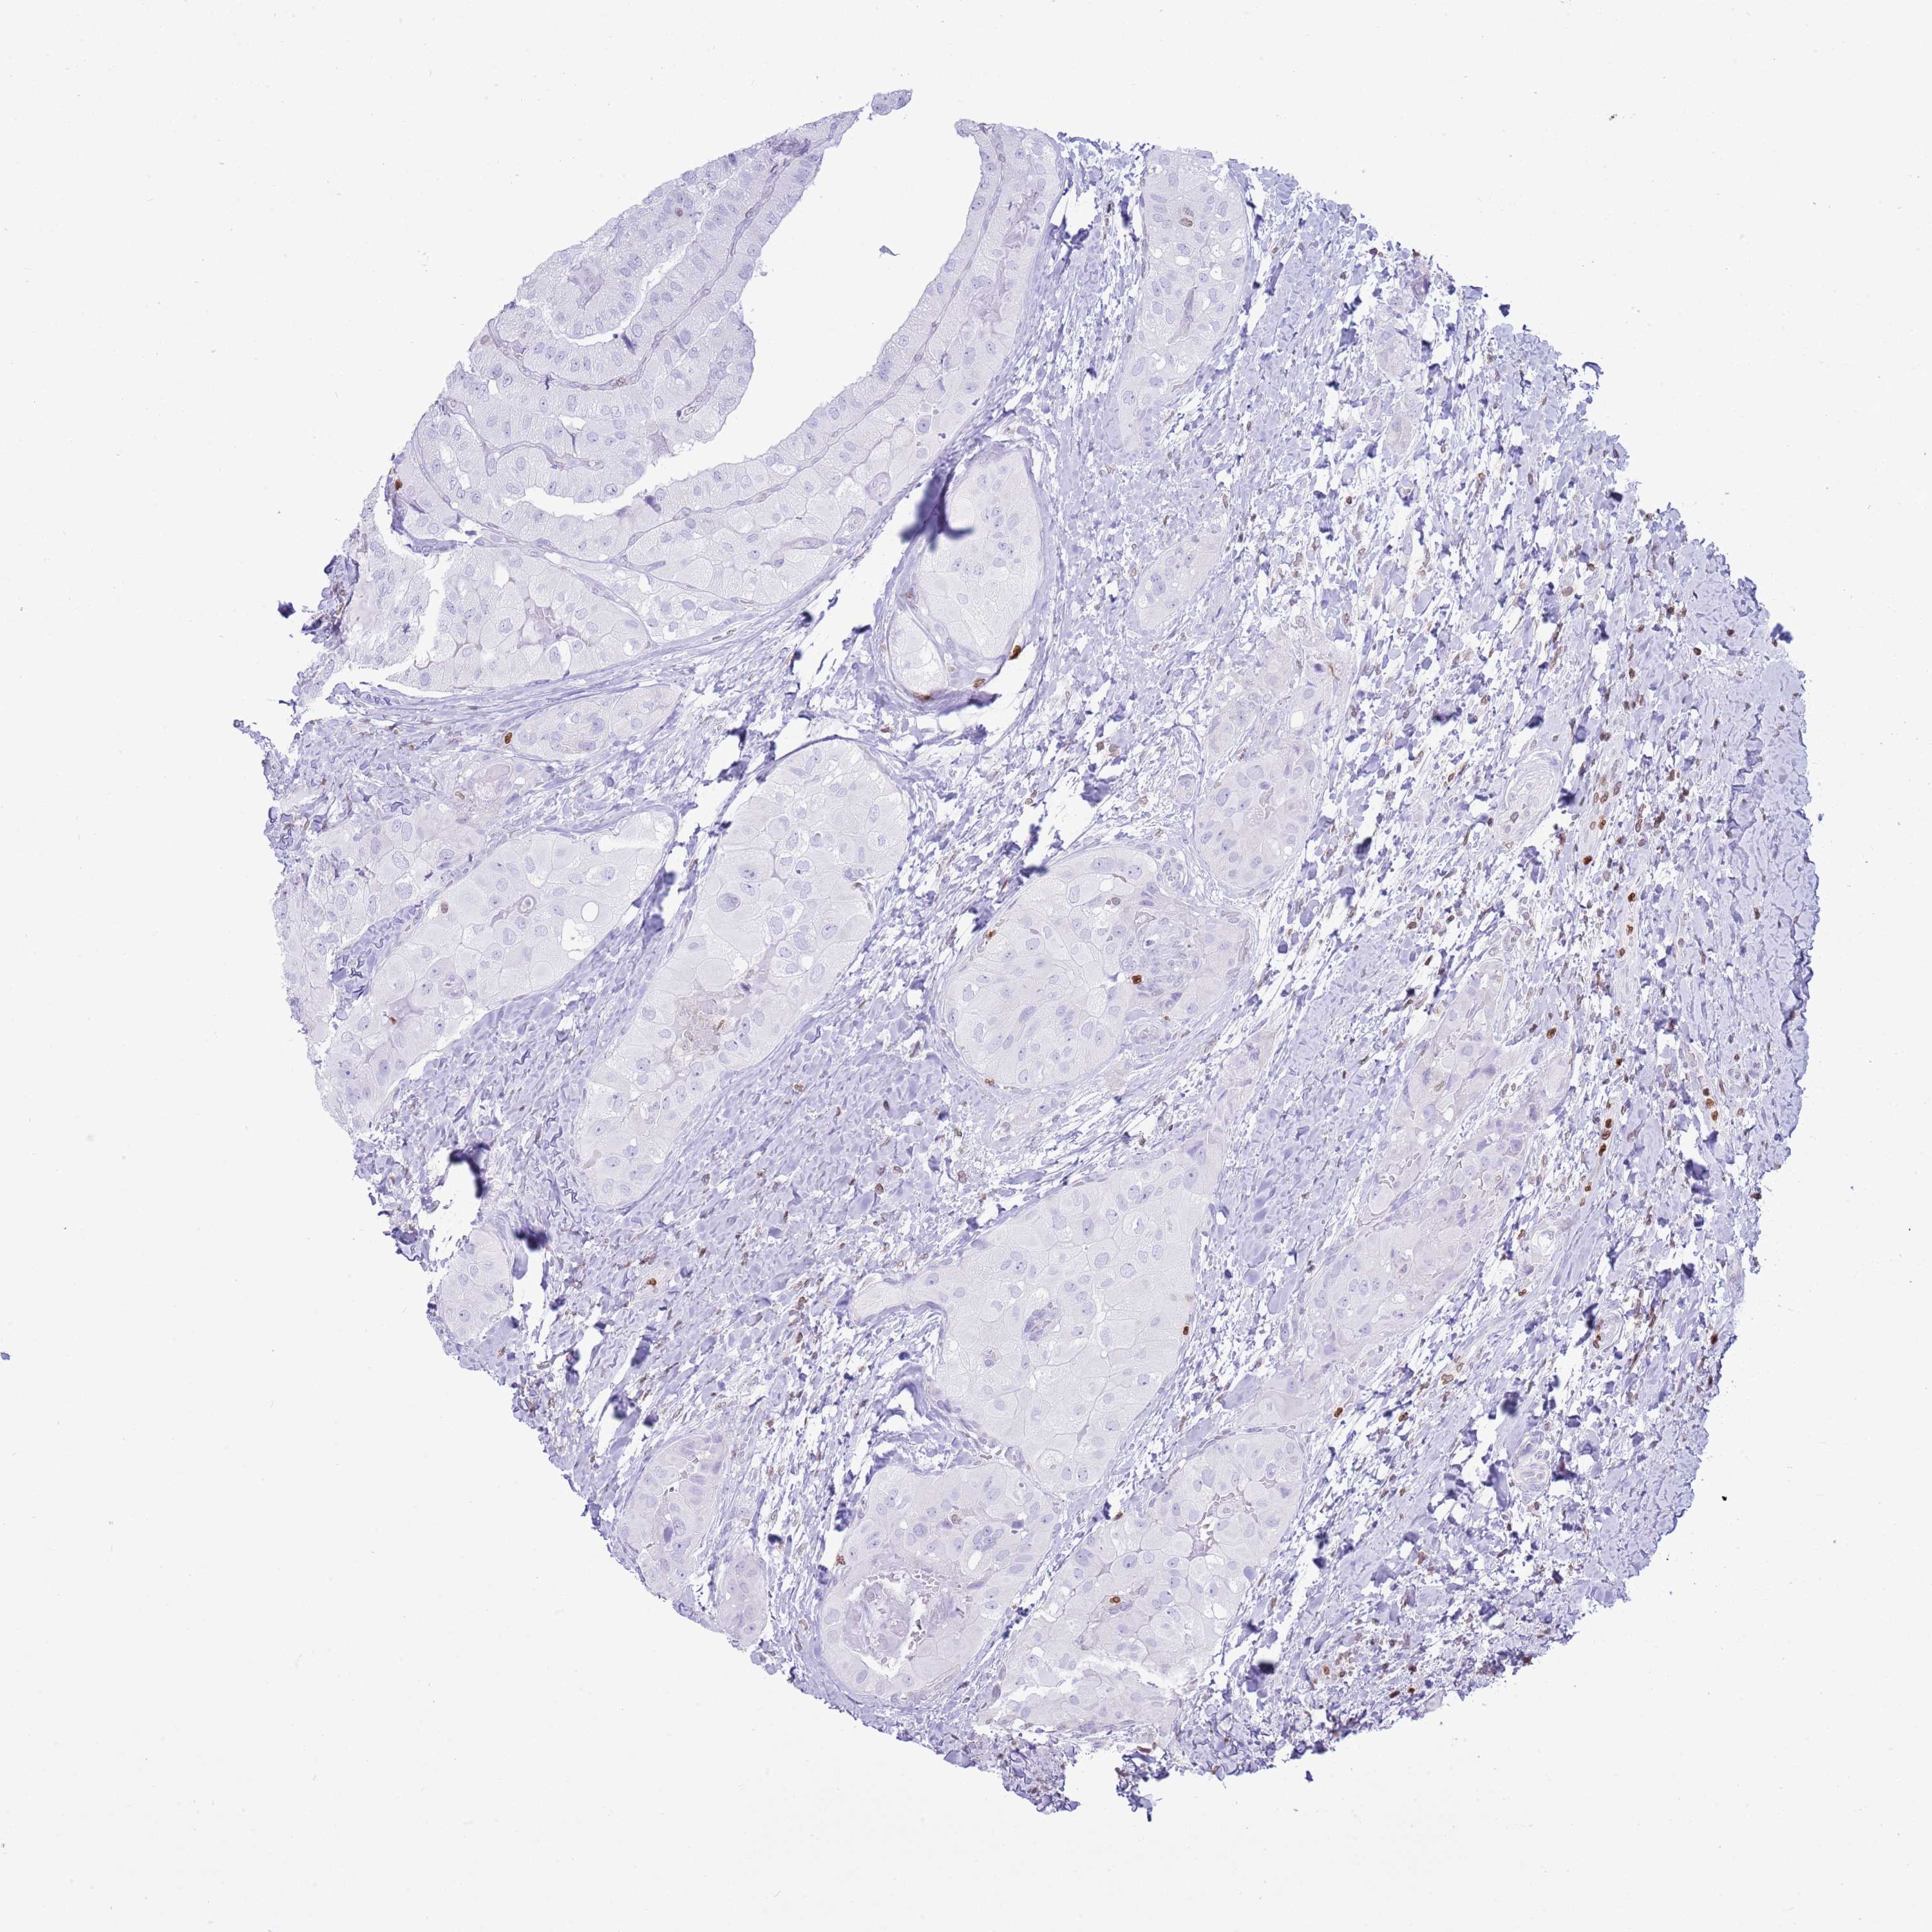

THYROID CANCER - Protein expressioni

A mouse-over function shows sample information and annotation data. Click on an image to view it in a full screen mode. Samples can be filtered based on level of antibody staining by selecting one or several of the following categories: high, medium, low and not detected. The assay and annotation is described here.

Note that samples used for immunohistochemistry by the Human Protein Atlas do not correspond to samples in the TCGA dataset.

Antibody stainingi

Antibody staining in the annotated cell types in the current human tissue is reported as not detected, low, medium, or high, based on conventional immunohistochemistry profiling in selected tissues. This score is based on the combination of the staining intensity and fraction of stained cells.

Each image is clickable and will lead to virtual microscopy that enables deeper exploration of all samples and also displays staining intensity scores, fraction scores and subcellular localization as well as patient and tissue information for each sample.

Antibody HPA049840

Antibody HPA062236

Staining

High

Medium

Low

Not detected

Intensity

Strong

Moderate

Weak

Negative

Quantity

>75%

75%-25%

<25%

None

Location

Nuclear

Cytoplasmic/membranous

Cytoplasmic/membranous,nuclear

Papillary adenocarcinoma, NOS

Follicular adenoma carcinoma, NOS